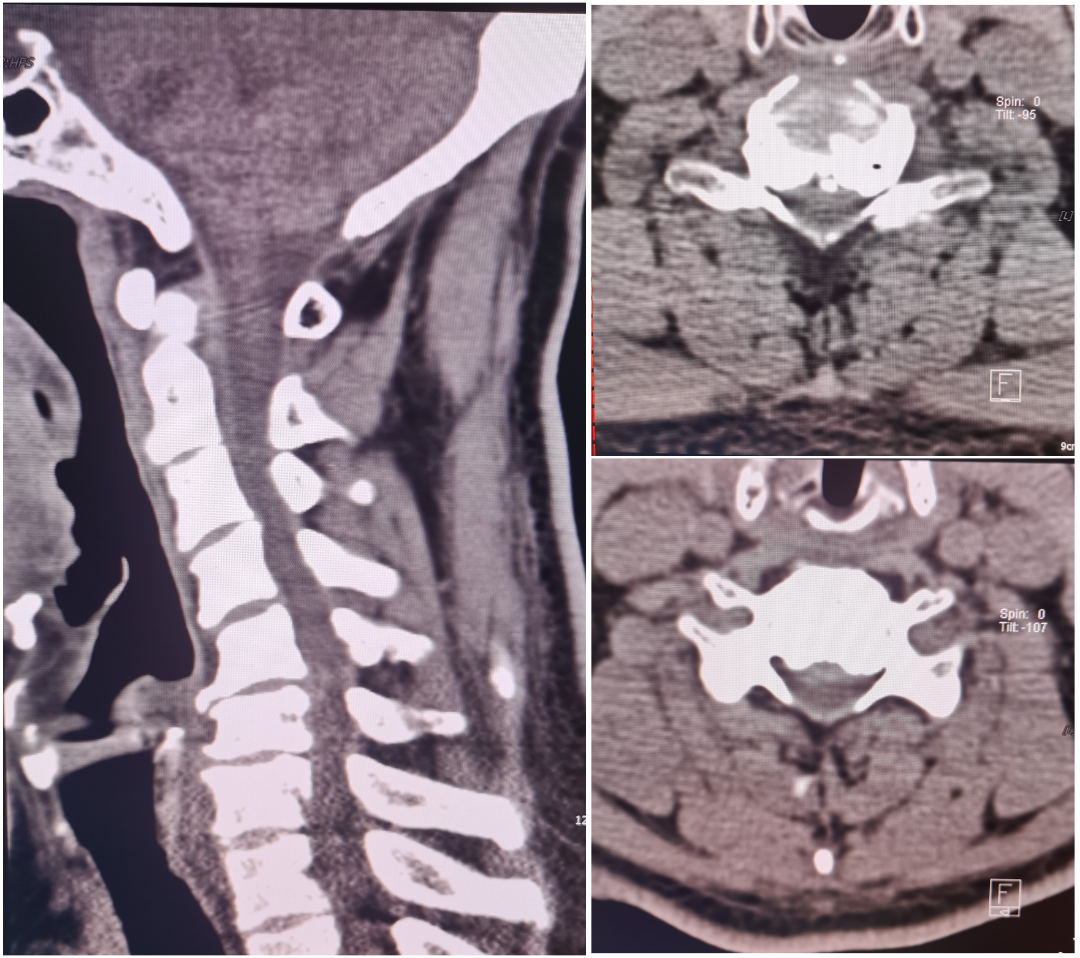

患者何某,中年女性,陈旧性枢椎齿状突骨折并寰枢关节脱位(难复性),入院是四肢不全瘫,生活不能自理;术前经大重量颅骨牵引不能复位(图三),于全麻行单一后路切开松解、寰椎后弓部分切除减压、经自制“Z”形复位棒复位、椎弓根螺钉内固定,术中透视见寰枢关节脱位完美复位,术后患者疾病症状改善。

术前影像:枢椎此状图陈旧骨折并寰枢关节脱位、脊髓明显受压

术中透视:骨折脱位复位满意

术后复查影像检查:脱位复位,椎管明显恢复